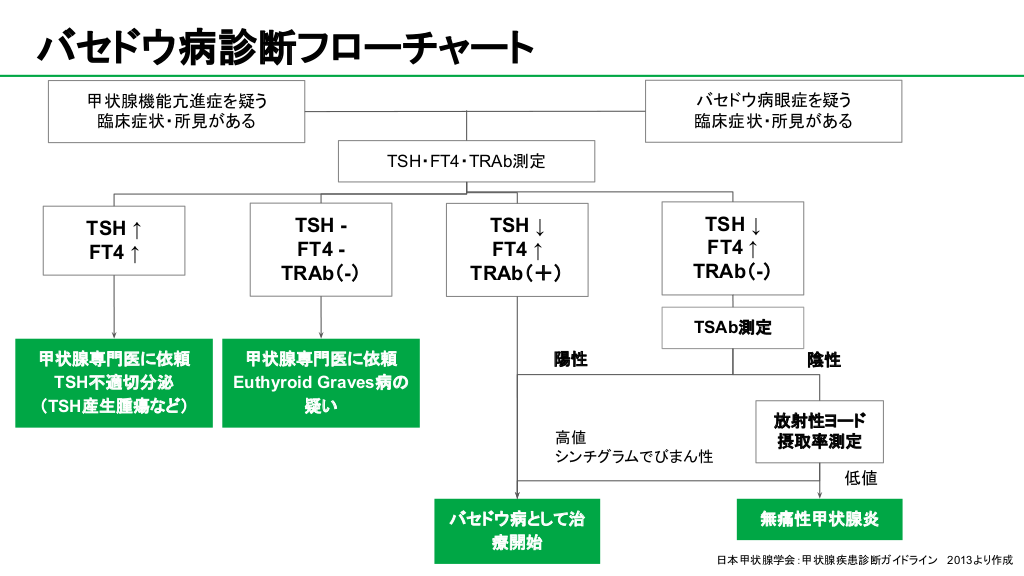

診断方法

医師があなたが潜在性甲状腺機能亢進症であると疑う場合、まずあなたのTSH レベルを評価します。

これらの検査を実行するには、医師は腕から血液サンプルを採取する必要があります。

成人におけるTSHの正常基準範囲は、通常、1リットルあたり0.4~4.0ミリ国際単位(mIU/L)と定義されています。ただし、検査レポートに記載されている基準範囲を常に参照することが重要です。

無症候性甲状腺機能亢進症は、一般に 2 つのカテゴリーに分類されます。

- グレード I:低いが検出可能な TSH。このカテゴリーに属する人々の TSH レベルは 0.1 ~ 0.4 mlU/L です。

- グレード II: TSH が検出されない。このカテゴリーに属する人々は、TSH レベルが 0.1 mlU/L 未満です。

医師はあなたの潜在性甲状腺機能亢進症の原因を診断します。原因を特定することは、適切な治療法を決定するのに役立ちます。

バセドウ病による潜在性甲状腺機能亢進症がある場合は、治療が必要です。医師はおそらく放射性ヨウ素療法またはメチマゾールなどの抗甲状腺薬を処方するでしょう。